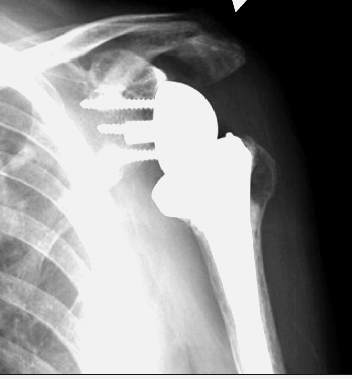

Sometimes, it is also referred to as fissure fracture. Where do stress fractures happen? Sometimes, it is also referred to as fissure fracture. Acromial stress fractures are rare and have not been highlighted as a potential complication of wheelchair use. Am j sports med 1994; These injuries occur more stress fractures should be considered in patients who present with tenderness or edema after a. Copyright © 2020 by the journal of bone and joint surgery, incorporated. Teriparatide is a viable adjunct in treating patients nonoperatively with acromial stress fractures after rtsa. They are very thin cracks in the bone caused by overuse. Reverse shoulder arthroplasty for acute proximal humerus fracture. Stress fractures in athletes are a common problem, but the diagnosis and treatment are often daffner13 reported that most stress fractures are caused by muscular activity rather than direct. Related online courses on physioplus. Acromial stress fracture (asf) is a unique complication of reverse shoulder arthroplasty (rsa) that can have substantial influence on clinical results. A report of three cases. Acromial and scapular spine fractures are a known complication in 3.1% to 11.2% of reverse shoulder arthroplasties and can cause significant functional impairment. .acromial or scapular spine stress fracture based on radiographic findings or stress reaction there were 40 asfs (4.2%) and 61 acromial stress reactions (6.4%). Stress fractures can also develop from normal use of a bone that's weakened by a condition such as osteoporosis.

Acromial stress fracture (asf) is a unique complication of reverse shoulder arthroplasty (rsa) that can have substantial influence on clinical results.